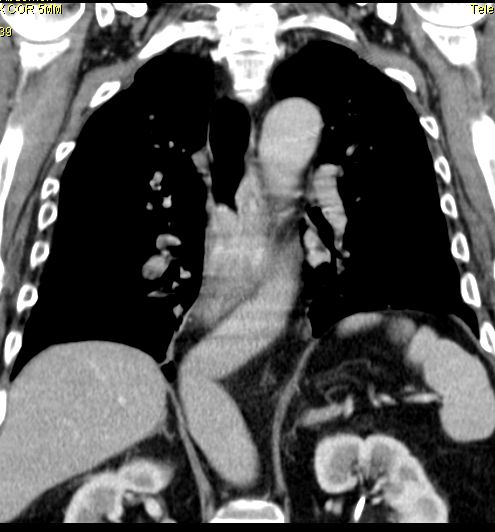

Lokale Ausbreitung im Mediastinum, Lymphnoten-Metastasen in der CC-Achse, Lungen- und Lebermetastasen.

Endoskopie mit Biopsie, Rö.-Breischluck, CT oder MRT